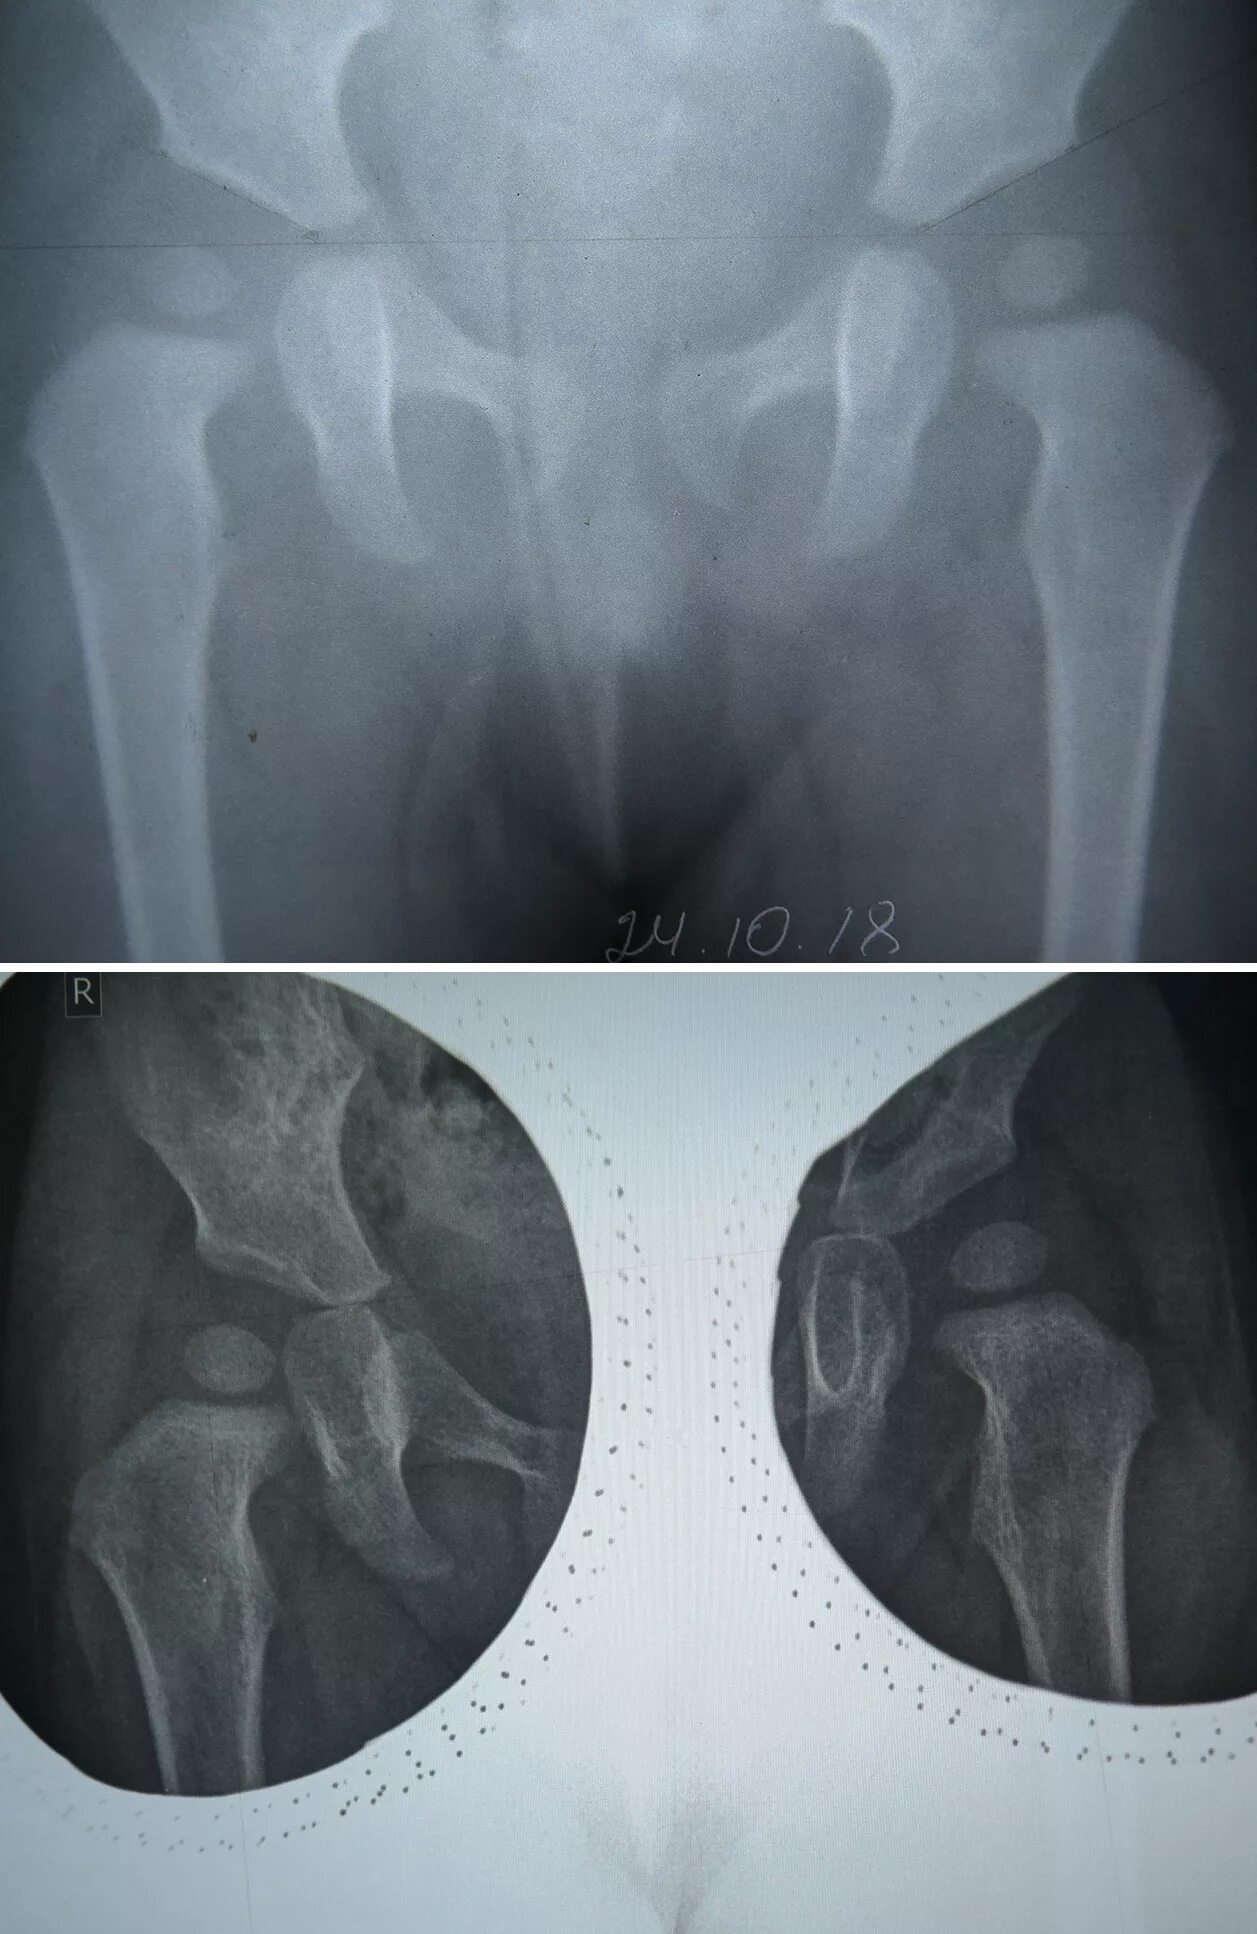

Дисплазия 7 лет